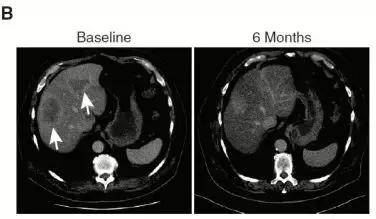

FoundationOne®检测胃癌中临床相关变异和新的靶向路径.

(二)胃癌患者检测到FGFR2扩增,患者对FGFR2*制剂抑**AZD4547有效,治疗6个月后,肝转移灶基本消失。